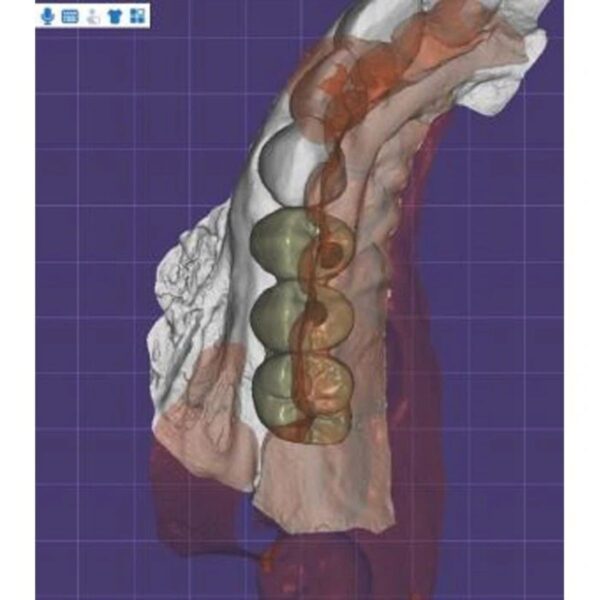

Dental Crown Design

Full contour zirconia, E.max, Copings, and Bridges. Perfect margins guaranteed.

Implant Crown Design

Custom Abutments, Screw-Retained Crowns, and Hybrid Bars. We verify emergence profiles.